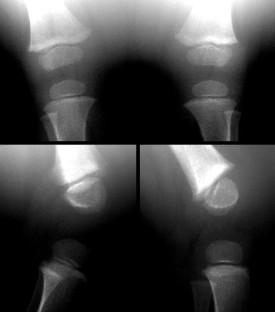

Neonatal physeal fracture of the distal femur is often difficult to diagnose. Timely and accurate diagnosis and appropriate therapy are critical in order to avoid permanent morbidity and dysfunction of the affected limb. We describe an infant in whom closed reduction and pinning were required in order to assure a good outcome.